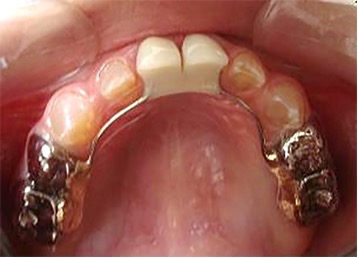

En el año 2010, el mantenedor de espacio fijo superior se descementó, pero debido a la cercana erupción de los incisivos centrales superiores permanentes obser-vada radiográficamente (Figura 5), se decidió no recementarlo, confeccionando coronas de acero independientes en los 4 molares superiores primarios (5.4, 5.5, 6.4 y 6.5) y en el 7.5, previa restauración de las lesiones de caries con ionómero vítreo (Figura 6). Cuando se observó la erupción del 4.1 y 3.1, y de los 4 molares permanentes, se realizaron 3 aplicaciones de barniz de fluoruro de sodio al 5%, cumpliendo con los protocolos establecidos.

Figura 5: Examen clínico intraoral superior, sector anterior y radiografía panorámica año 2010.